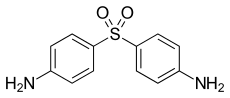

Mycobacterium leprae was sensitive to dapsone as a treatment alone, but since the 1960's, it has developed resistance against this antibiotic. Currently, a multidrug treatment (MDT) is recommended by the World Health Organization, including dapsone, rifampicin, and clofazimine. The species was discovered in 1873 by the Norwegian physician Gerhard Armauer Hansen, and was the first bacterium to be identified as a cause of disease in humans.[8]

The mycolic acids in the bacteria's cell walls afford resistance to many antibiotics and are a major virulence factor.[49] Multidrug therapy (MDT) was recommended by WHO Expert Committee in 1984, and became the standard leprosy treatment. MDT has been supplied by WHO for free since 1995 to endemic countries. MDT is used to treat leprosy because treatment of leprosy with one drug (monotherapy) can result in drug resistance. The drug combination used in MDT will depend on the classification of the disease. WHO recommends patients with multibacillary leprosy use a combination of Rifampicin, Clofazimine, and Dapsone for 12 months. WHO recommends patients with paulibacilalry leprosy use combination of Rifampicin and Dapsone for a duration of 6 months.[50] Antibiotics must be taken regularly until treatment is complete because Mycobacterium leprae can become drug resistant.[51] Effectiveness of the treatment can be determined with the use of an acid-fast stain of Mycobacterium leprae from a skin smear to estimate the number of bacilli still present in the patient.[52]

A preventive measure of Mycobacterium leprae is to avoid close contact with infectious people who are untreated.[53] Blindness, crippling of the hands and feet, and paralysis are all effects of nerve damage associated with untreated M. leprae. Treatment does not reverse the nerve damage done, which is why early treatment is needed.[51] The Bacillus Calmette–Guérin vaccine offers a variable amount of protection against leprosy in addition to its main target of tuberculosis.[54]

Dapsone competitively inhibits the enzyme dihydropteroate synthase (DHPS) resulting in decreases the production of tetrahydrofolate, which is an essential component of nucleic acid biosynthesis in M. leprae. Rifampin will interrupt binding of the β-subunit of the DNA-dependent RNA polymerase, which will uncouple mRNA production and results in cell death. Clofazimine's mechanisms are not fully understood regarding Mycobacterium leprae, but the drug's binding appear to occur at base sequences with guanine, which may explain why clofazimine has a preference for G+C rich genomes of mycobacteria over human DNA. The binding of clofazimine to mycobacterial DNA can has been proven as weakly bactericidal against Mycobacterium leprae in mice, which is why it is not suitable for single drug therapy for leprosy. Out of the three main drugs rifampin is more bactericidal than either dapsone or clofazimine.[55]

Antibiotic resistance

Resistance to antibiotics is seen in around 10% of new cases of leprosy and in around 15% of relapsed cases.[57] Drug resistance in Mycobacterium leprae is thought to be from genetic alterations in the antibiotic targets and a reduction in cell wall permeability.[58] Compared to the amount of efflux pumps in M. tuberculosis, Mycobacterium leprae contains about half as many. The efflux pumps contributing to drug resistance and virulence in M. tuberculosis have been retained throughout the genome reductive evolution that Mycobacterium leprae underwent.[58]